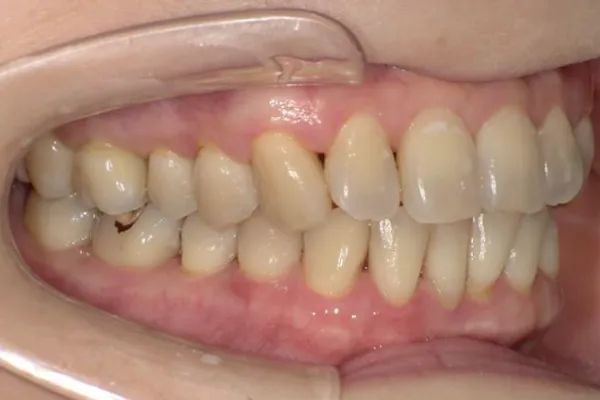

歯周組織再生療法

歯周病で失われた骨や歯ぐきを“再び回復させる”ための治療です。歯を支える力を取り戻し、将来的な抜歯のリスクを減らすことにつながります。

歯を残す最新治療

歯周病により破壊された、歯茎や骨を人工骨や成長因子などを用いて再生させる治療方法です。

将来的に抜歯となるリスクの高い歯などを歯周組織を再生させ、歯を長持ちさせることを目的とします。歯周病でダメになった歯をどうしても残したい方、歯ぐきや歯槽骨を元に戻して歯の寿命をしっかり伸ばしたい方に適応される治療方法です。 -